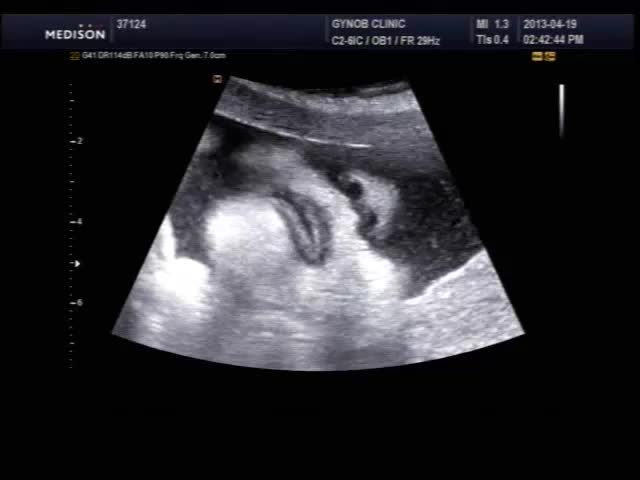

오늘 초음파 보신 산모의 영상인데 태아의 입과 인중 부분이 잘 보이는 편이라 여러분들께 보여드릴 겸, 그리고 설명 드릴 것도 있고 해서 올려 봅니다.

초음파 검사시 태아의 입과 인중을 살펴보는 것은 구순열과 같은 기형이 있는가 보는 목적이며 요즘은 초음파 장비 기술이 발달하여 비교적 쉽게 중기에 진단이 가능합니다.

태아는 뱃속에서도 보고 듣고 먹고 다 할 수 있는데 위 영상을 보시면 태아가 입을 오물거리면서 무언가를 말하는 것도 같지만 사실 말을 하는 것은 아니고 음식을 먹는 운동을 하면서 실제 양수를 삼키는 모습입니다.